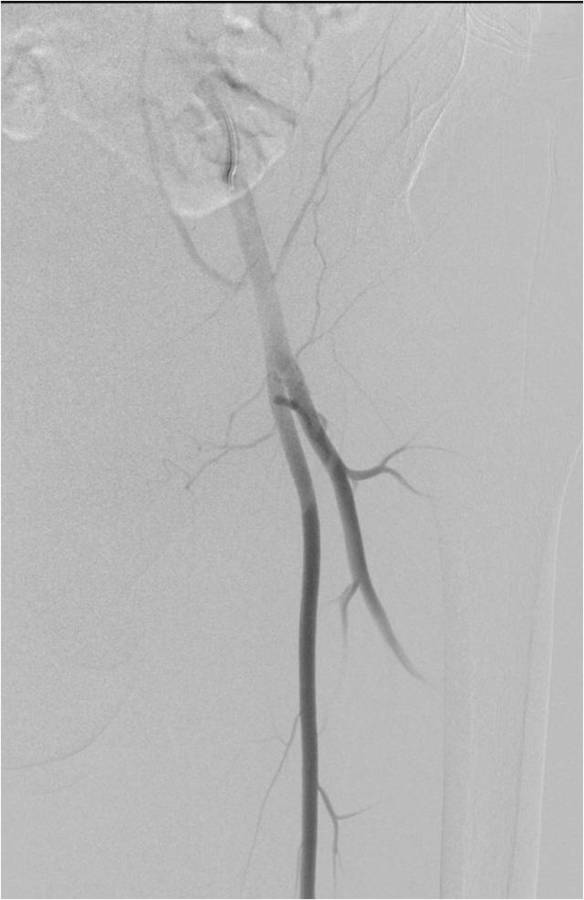

Gallery of Unlabled Radiographs from Lecture (Dr. French) - 2020

Click a thumbnail to enter the gallery display. Click the file name link at the bottom left of the gallery display to view the image at high resolution.